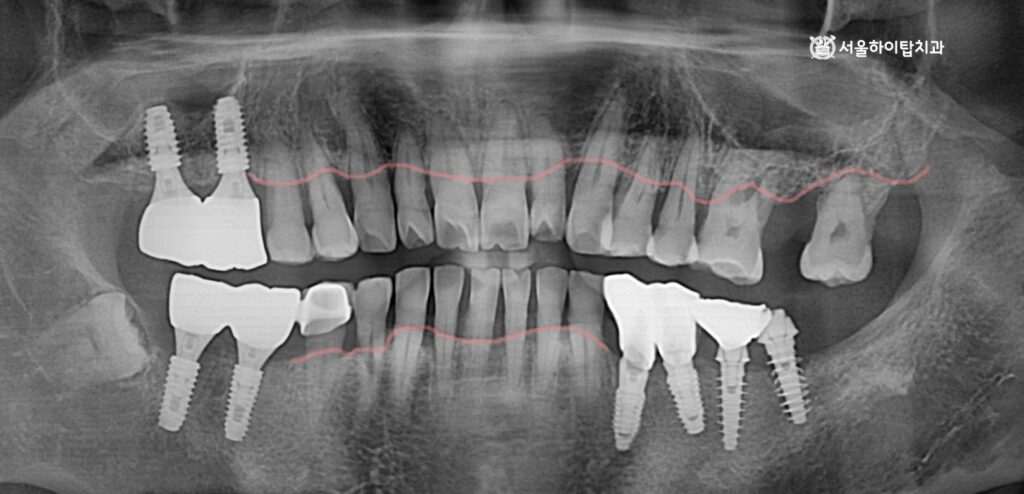

전반적으로 진행 중인 치주염과 치조골 흡수

간석역 치과 에서 임의로 표시해 둔 선을 보시면,

임플란트가 식립된 부위를 제외하고 전반적으로 치조골 흡수가 진행된 양상을 확인할 수 있습니다.

특히 어금니에만 임플란트가 식립된 모습을 볼 수 있는데,

이는 어금니가 씹는 힘을 가장 많이 받는 부위인 동시에

칫솔질이 어렵고 음식물이 잘 끼어

치주염이 가장 먼저, 그리고 가장 심하게 진행되기 쉬운 위치이기 때문입니다.

반면 앞니는 상대적으로 늦게까지 남아 있는 경우가 많아,

이처럼 어금니에만 식립된 소견이 임상에서 흔하게 관찰됩니다.

이러한 양상은 과거 또는 현재에

전반적인 치주염이 진행되었을 가능성을 시사하며,

현재 남아 있는 자연치 역시

지속적인 치주 관리와 정기적인 검진이 필요한 상태임을 의미합니다.